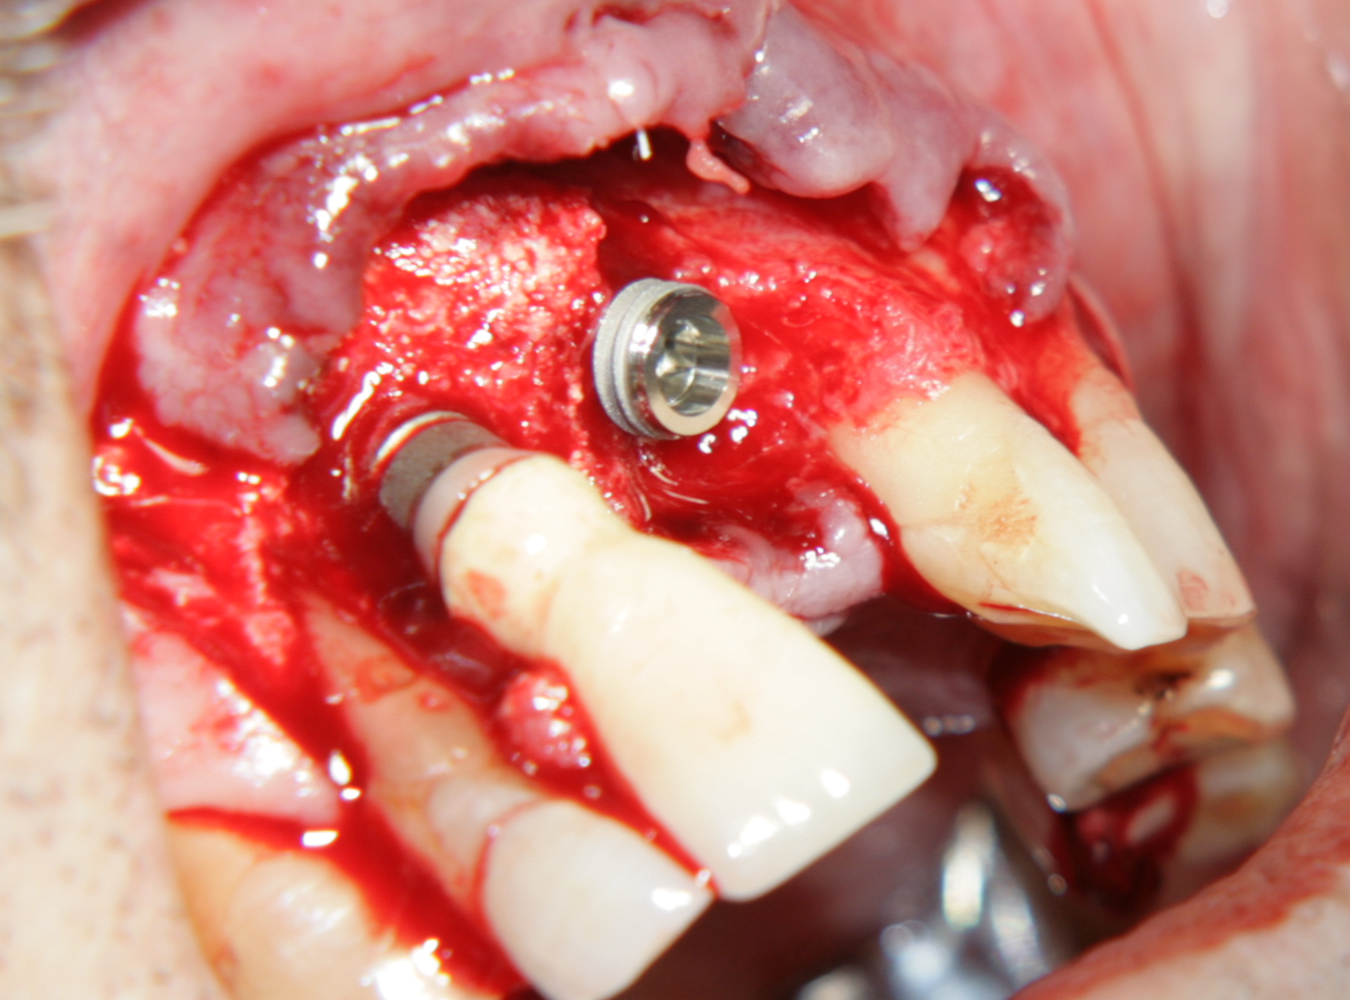

Tent screw - винтове за

фиксиране на титановата мрежа

Около винтовете се поставя костозаместител, добре е да се размеси с

автогенна кост

Титанова мембрана